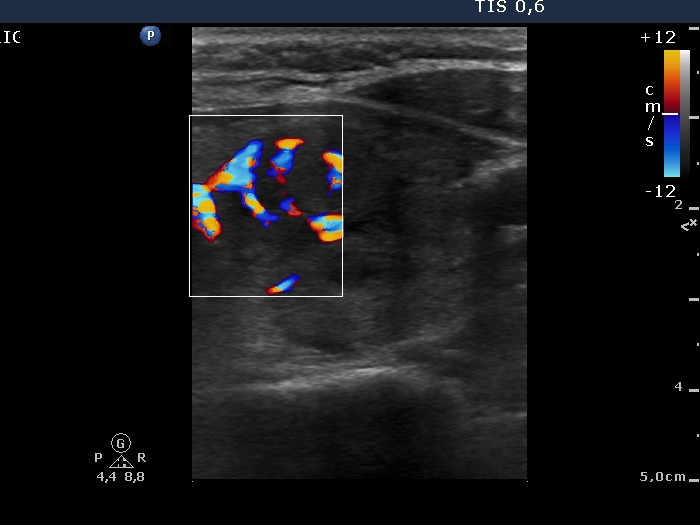

Ultraosonography: the left lobe presented a large nodule composed of several discrete lesions. The intranodular vascularization was increased.